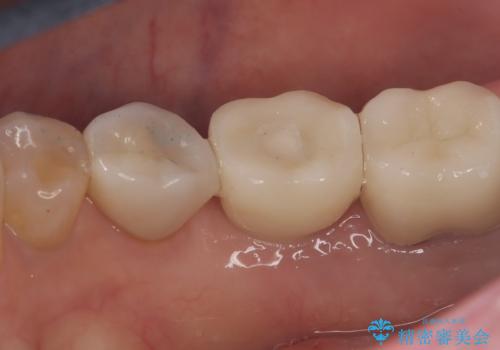

- 主訴:右下のセラミックのブリッジが何度も同じところで折れて壊れてしまう。

対合歯との咬合関係において、右下7番目と6番目の被せものの連結部がたわみやすい環境にあったため、ブリッジの新製ではなくインプラント治療を行いすべての歯を単冠仕上げとすることにしました。

何度も右下6、7間でブリッジが折れてしまうとのことでした。対合歯とブリッジの連結部が強く当たりたわみやすい状態でした。破折しずらい金属を使用したブリッジの選択もありましたが、支台歯(右下7)が失活歯場合、破折リスクが高く、破折してしまった場合にまたブリッジを外しての再治療になってしまう可能性を説明したところ、全て単冠仕上げとできるインプラント治療を希望されました。

右下5番のクラウンは、ブリッジを切断しそのまま使用していただいています。